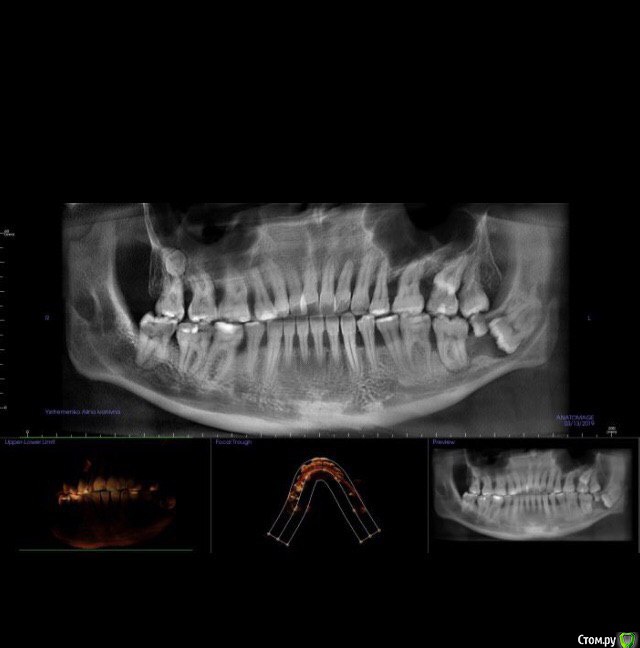

yefremovna Опубликовано 19 мая, 2019 Поделиться Опубликовано 19 мая, 2019 Добрый день!Первый раз в жизни делала КТ челюсти. Оказалось, кроме восьмерок есть и девятки. Никогда не беспокоили не восьмерки, не девятки.Что делать теперь с находкой, всё удалять? Ссылка на комментарий

red_butler Опубликовано 20 мая, 2019 Поделиться Опубликовано 20 мая, 2019 Внизу слева удалять Ссылка на комментарий

yefremovna Опубликовано 20 мая, 2019 Автор Поделиться Опубликовано 20 мая, 2019 Внизу слева удалять а остальные? их не придется удалять позже? Ссылка на комментарий

red_butler Опубликовано 20 мая, 2019 Поделиться Опубликовано 20 мая, 2019 а остальные? их не придется удалять позже?со временем возможно и придется Ссылка на комментарий